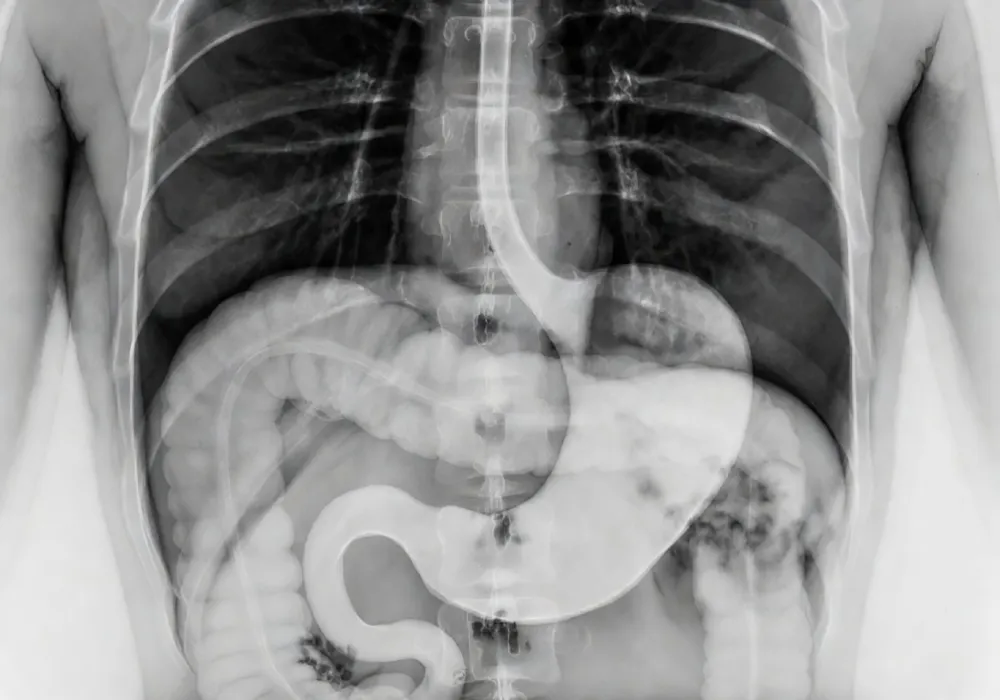

فلوروسکوپی، اندامهای داخلی بدن مثل قلب، معده و دستگاه گوارش را بهصورت زنده به تصویر میکشد. یعنی پزشکان میتوانند تصاویر متحرک از داخل بدن را در لحظه و بهصورت ویدئویی مشاهده کنند. برای مثال با فلوروسکوپی قلب میتوان در لحظه باز و بسته شدن دریچهها و مسیر هدایت کاتترها در حین درمان را مشاهده کرد.

به کمک این روش، پزشک فقط یک تصویر ثابت نمیبیند، بلکه عملکرد واقعی عضو را همانطور که اتفاق میافتد زیر نظر دارد. در ادامه بررسی میکنیم که کاربرد فلوروسکوپی چیست، در چه شرایطی استفاده میشود و چرا در تشخیص و درمان بسیاری از بیماریها موثر است.

فلوروسکوپی یک روش تصویربرداری پزشکی است که تصاویر زندهای از بدن ایجاد میکند. پزشکان با استفاده از این تصاویر میتوانند نحوه حرکت اندامها، عبور مایعات، جریان خون در رگها و واکنش بافتها را در زمان واقعی مشاهده کنند و سپس برای تصمیمگیریهای پزشکی مانند تشخیص دقیق بیماری، انتخاب روش درمان مناسب یا هدایت اقدامات درمانی کمتهاجمی اقدام کنند. این دستگاه از هشت بخش اصلی تشکیل شده که در کنار هم امکان مشاهده اعضای درونی بدن را فراهم میکنند.

- فلوروسکوپی معده و دستگاه گوارش: بررسی مری، معده و روده با بلع باریم یا انما.

فلوروسکوپی یک روش تصویربرداری پزشکی است که وظیفه آن نمایش لحظهای اندامهای داخلی بدن، مثل قلب، ریه یا دستگاه گوارش است تا پزشکان بتوانند با دید دقیقتری تشخیص دهند و درمان را هدفمندتر پیش ببرند. برای مثال، با فلوروسکوپی مری میتوان نحوه بلع و حرکت مواد غذایی را بهطور کامل بررسی کرد.